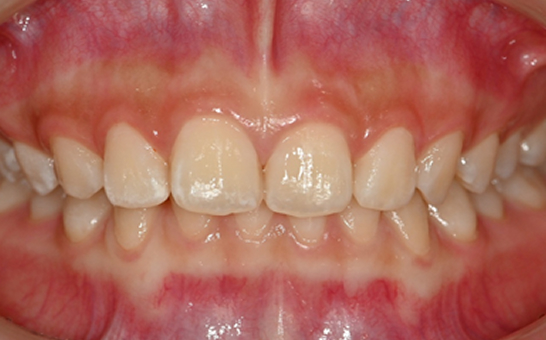

인비절라인 퍼스트(Invisalign First)는 어린이와

성장기 청소년을 위한 투명 교정 장치로, 치아와 턱뼈가

성장하는 과정에 맞춰 설계된 교정 시스템입니다.

해당하는 증상이 있다면 전문의와 상담 후 조기 교정 시

성장기 어린이에게 교합이 틀어지는것을 미리 예방 할 수 있습니다.

※ 바른선택치과의원은 의료법을 준수하며 위 케이스는 실제 내원 환자분의 동의하에 공개된 사진과 동일한 환자분께 같은 조건에서 촬영한 사진을 활용했습니다.

개인에 따라 진료 및 치료 방법이 다르게 적용할 수 있으며, 효과와 부작용이 개인마다 다르게 나타날 수 있는 점을 안내해 드리며, 진료 전 전문의료진과 충분한 상담을 권해드립니다.